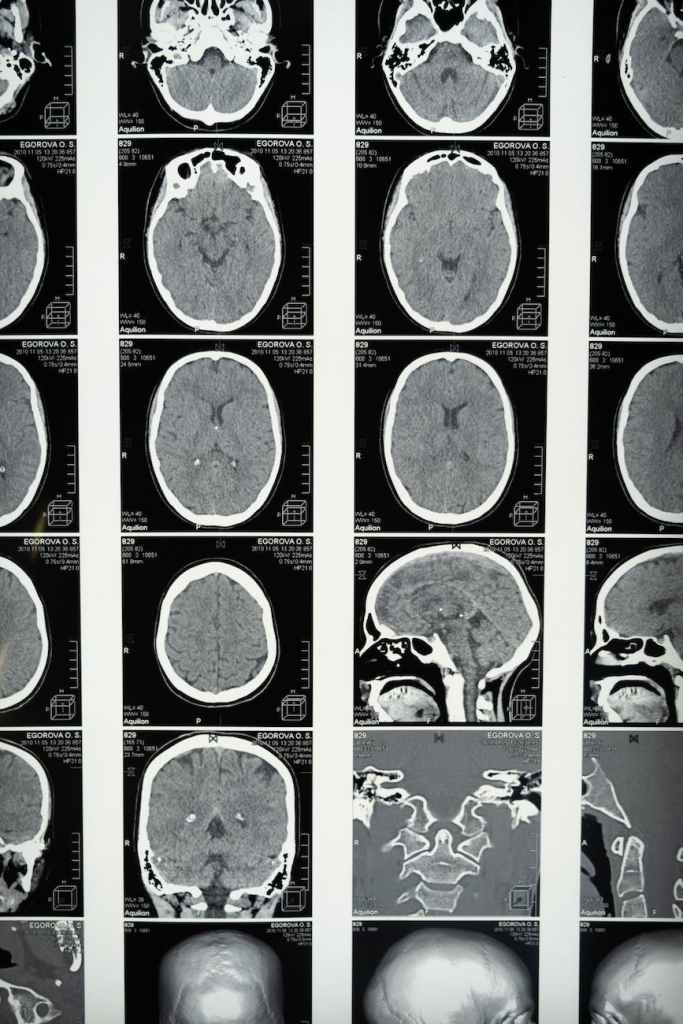

Special tests can help doctors identify the unique characteristics of glioblastoma on a molecular level. This information can support the creation of a personalized treatment plan.

The current standard of care for glioblastoma is maximum safe surgical resection followed by radiation and chemotherapy (including Temozolomide or Temodar). Several clinical trials are testing different combinations and approaches to improve patient outcomes.